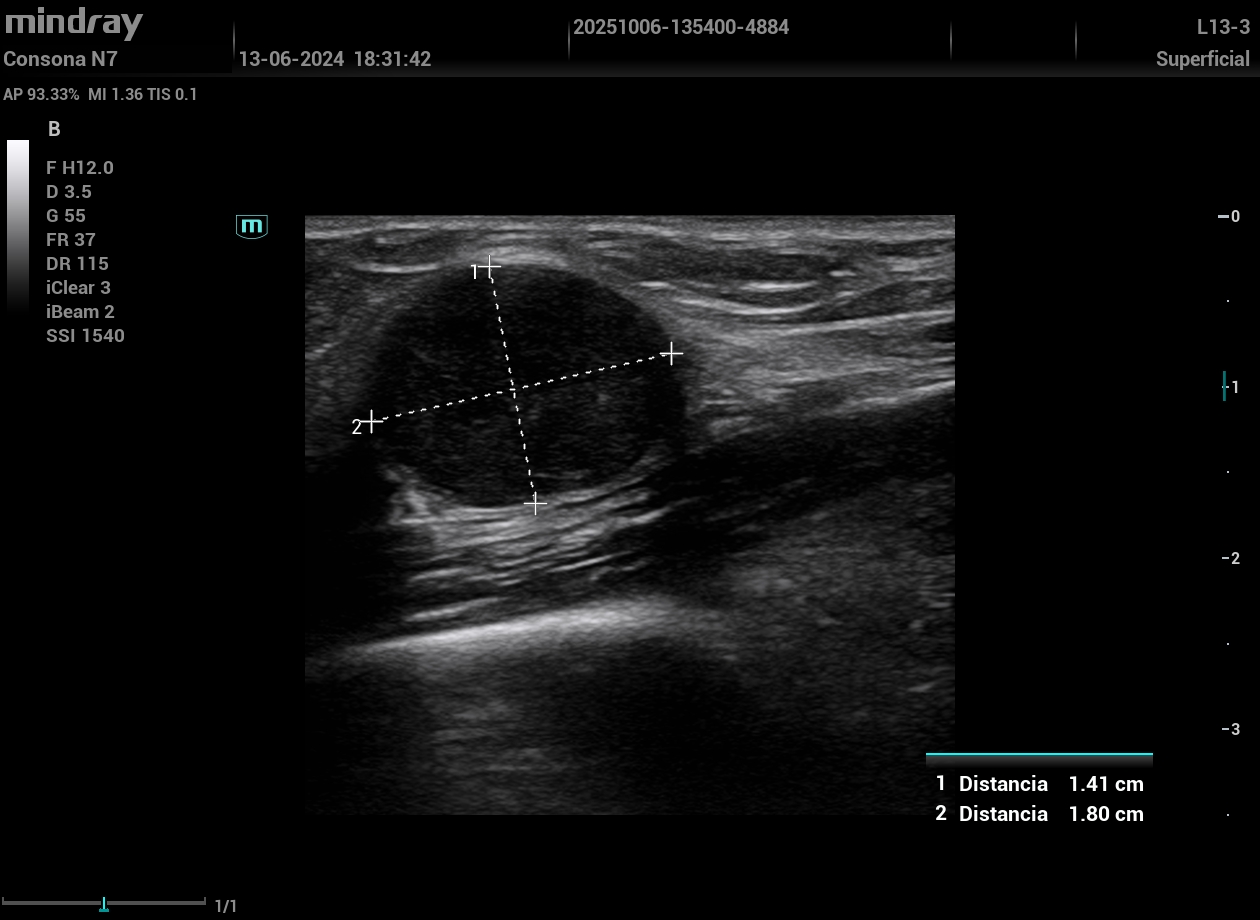

Inspirada por la rotación de una tutora en la Unidad de Riesgo Cardiovascular de un hospital, se formó al equipo en ecografía vascular e incorporó la técnica a la consulta. Se evaluó a 17 varones (50–65 años) que consultaron por disfunción eréctil sin enfermedad cardiovascular conocida y con RCV bajo-moderado por SCORE2. Se realizó una ecografía vascular aplicando el protocolo VASUS (arterias carótidas, femorales y aorta), identificando placas ateroscleróticas no detectadas antes. Estos hallazgos motivaron intensificar cambios en el estilo de vida, estrechar el seguimiento y ajustar tratamiento farmacológico.